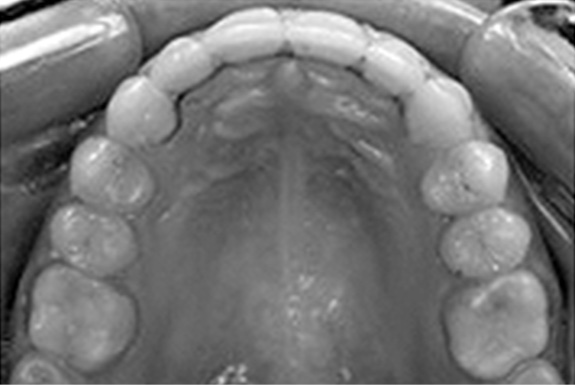

У пациентов с сочетанной патологией окклюзии зубных рядов с применением брекет-системы перед ее удалением из полости рта фиксировались несъемные проволочные ретейнеры на внутреннюю поверхность фронтальных зубов (рис. 3) и каппы (рис. 4).

Рис. 4. Ретенционная каппа.

Fig. 4. Retention mouthguard.